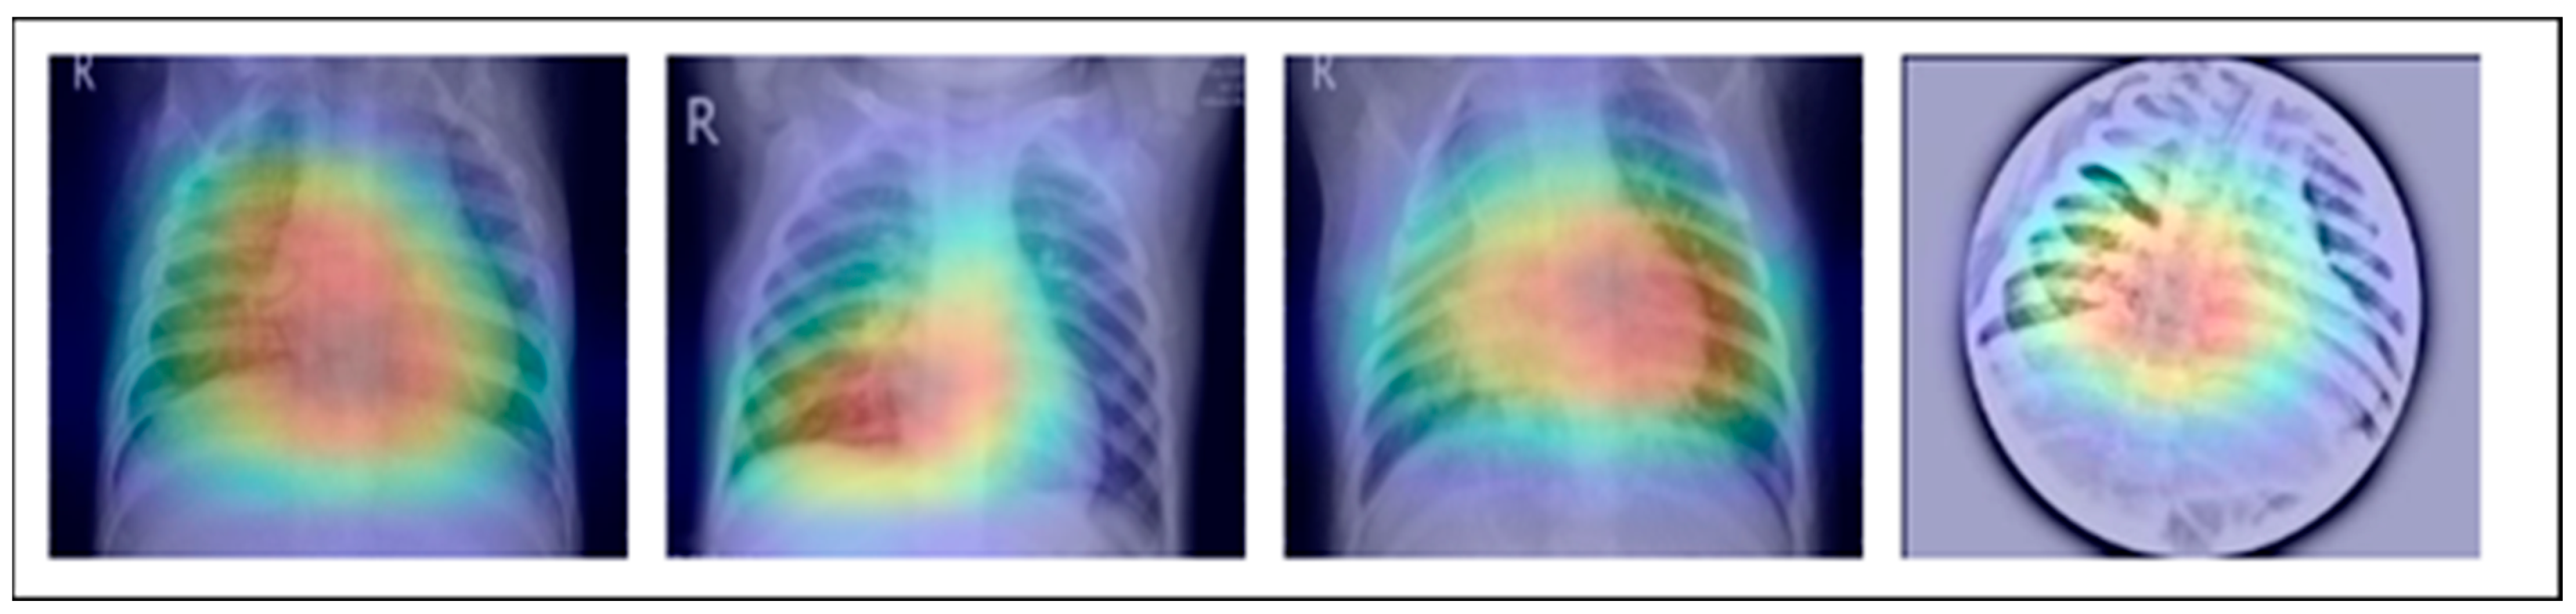

This extensive study gives important insights into the creation of DL models for the identification of pneumonia, TB, COVID-19, and lung cancer. They show how DL can reliably detect and categorize lung disorders, resulting in improved patient outcomes and more effective healthcare administration, as shown in Figure 1. We want to use the advances provided in these studies, as well as other relevant research, to construct a complete DL model for lung illness recognition and classification in this work. Our study aims to improve the accuracy, efficiency, and consistency of lung illness detection by analyzing varied datasets and applying cutting-edge approaches, ultimately leading to better patient care and treatment.

Meticulously inspected 13,313 lung photographs are shown in Figure 1. The three datasets that were used to build the training and testing fundus sets, each with a distinct dimension setting, are broken down in Table 3 and Table 4. All photos used in the experiment were downsized to 700 × 600 pixels, after which they were processed to create binary labels. A total of 13,313 photos made up the whole dataset, of which 3993 were used to evaluate the system. To guarantee neutrality, the dataset was initially converted into different classes by balancing the overall dataset number of photos both during and after the illness. Before being put into an algorithm created especially for the MixNet-LD model, the photos underwent pre-processing by being resized to 700 × 600 pixels. To lessen the variation between data points, the photos were also standardized. Data from Pak-Lungs is also used to train and assess the MixNet-LD system. Each image was initially saved with a resolution of 1125 × 1264 pixels.